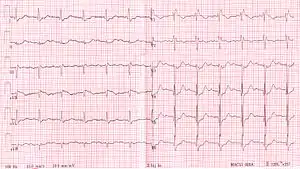

| ECG characteristics of a typical RBBB showing wide QRS complexes with a terminal R wave in lead V1 and a prolonged S wave in lead V6. | |

Diagnosis requires that the QRS complex is greater than 120 ms and an rsR' wave is present in lead V1 or V2.[2] The T waves are generally flipped in V1 and V2.[2] When the QRS duration is less than 120 ms, but the other criteria are present, it is called an incomplete RBBB.[1] Its presence does not interfere with the diagnosis of a heart attack.[1]

The criteria to diagnose a right bundle branch block on the electrocardiogram:

- The heart rhythm must originate above the ventricles (i.e., sinoatrial node, atria or atrioventricular node) to activate the conduction system at the correct point.

- The QRS duration must be more than 100 ms (incomplete block) or more than 120 ms (complete block).[4]

- There should be a terminal R wave in lead V1 (often called "R prime," and denoted by R, rR', rsR', rSR', or qR).

- There must be a prolonged S wave in leads I and V6 (sometimes referred to as a "slurred" S wave).

The T wave should be deflected opposite the terminal deflection of the QRS complex. This is known as appropriate T wave discordance with bundle branch block. A concordant T wave may suggest ischemia or myocardial infarction.

RBBB with associated first degree AV block

RBBB with associated first degree AV block RBBB with associated tachycardia

RBBB with associated tachycardia RBBB

RBBB